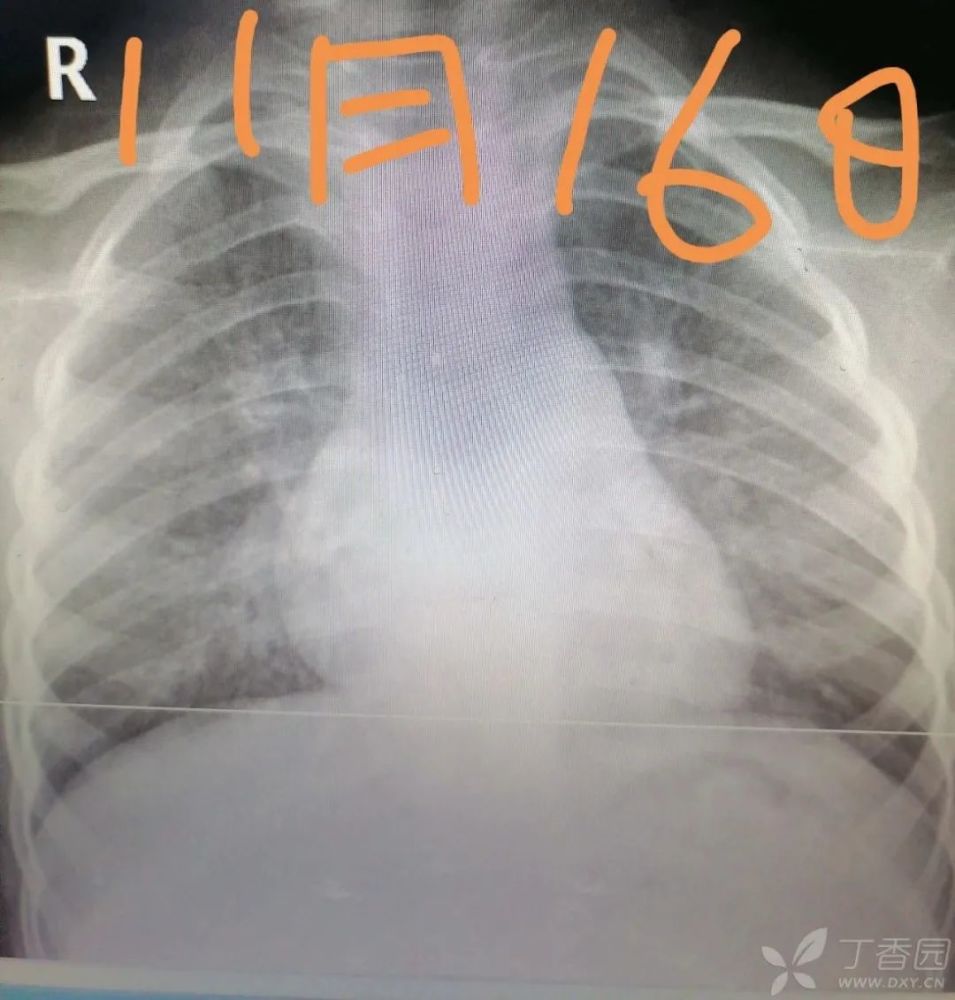

肺炎dr图片怎么看

肺炎dr图片怎么看,肺炎图片

患儿肺炎反复,难治,如何诊治?

影像诊断鉴别:肺癌,肺炎,肺结核

肺炎怎么看

厉害!看看如何利用dr做断层诊断新冠肺炎

下面这个肺部dr检测是什么意思.看图片,谢谢.

肺炎胸片

肺炎

肺炎症状